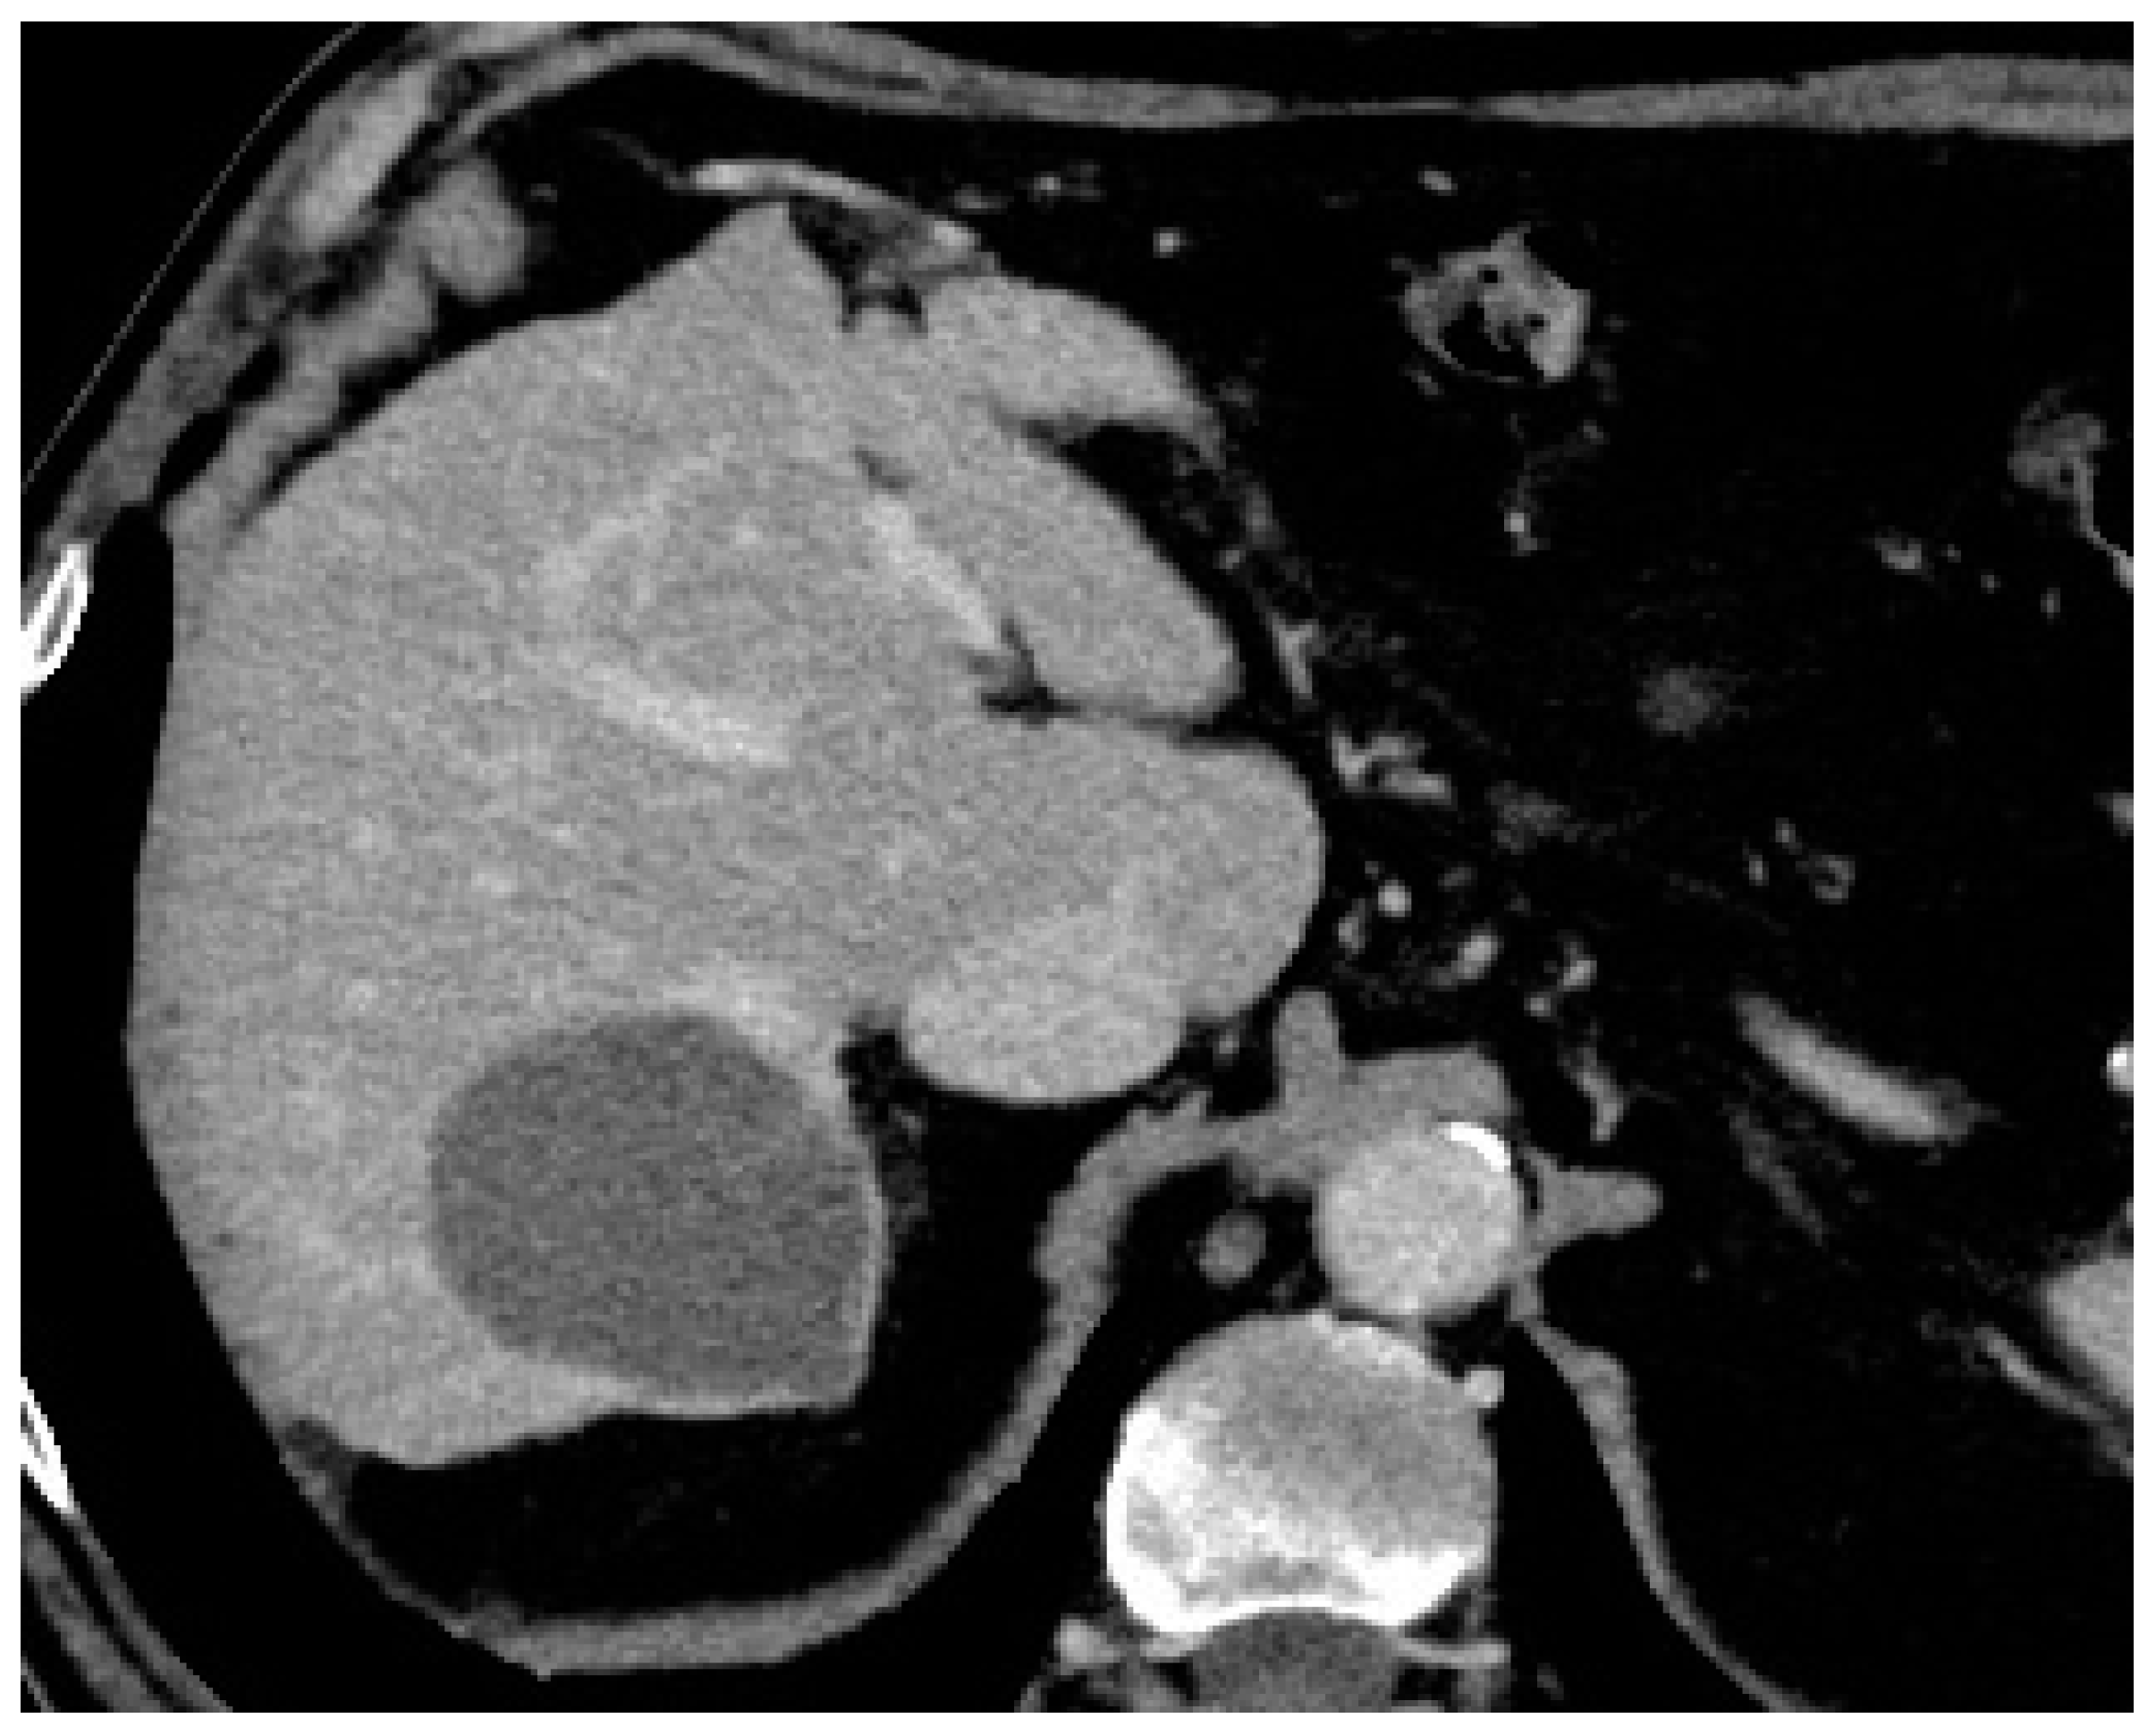

- Cornelis, F.H.; Korenbaum, C.; Ben Ammar, M.; Tavolaro, S.; Nouri-Neuville, M.; Lotz, J.P. Multimodal image-guided electrochemotherapy of unresectable liver metastasis from renal cell cancer. Diagn. Interv. Imag. 2019, 100, 309–311. [Google Scholar] [CrossRef] [PubMed]

- Spallek, H.; Bischoff, P.; Zhou, W.; De Terlizzi, F.; Jakob, F.; Kovàcs, A. Percutaneous electrochemotherapy in primary and secondary liver malignancies—Local tumor control and impact on overall survival. Radiol. Oncol. 2022, 56, 102–110. [Google Scholar] [CrossRef] [PubMed]

- Luerken, L.; Doppler, M.; Brunner, S.M.; Schlitt, H.J.; Uller, W. Stereotactic percutaneous electrochemotherapy as primary approach for unresectable large HCC at the hepatic hilum. Cardiovasc. Intervent Radiol. 2021, 44, 1462–1466. [Google Scholar] [CrossRef]